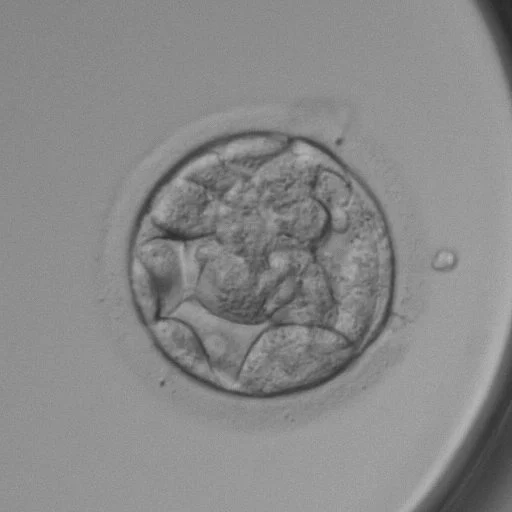

Thụ tinh trong ống nghiệm là một bước tiến hiện đại giúp các cặp vợ chồng vô sinh – hiếm muộn có được con của chính mình. Trong kĩ thuật này trứng được cấy thụ tinh trực tiếp với tinh trùng bên ngoài cơ thể để tạo thành phôi trước khi chuyển vào tử cung. Trong một chu kỳ chọc hút trứng, nhiều phôi được tạo thành và đánh giá chất lượng dựa trên hình thái và tốc độ phát triển để chuyển vào tử cung.

Xét nghiệm phân tích di truyền trước chuyển phôi (PGT – Preimplantation Genetic Testing) là kỹ thuật đi sâu vào phân tích di truyền bên trong của phôi, để dựa vào đó chọn lọc những phôi hoàn toàn bình thường, khỏe mạnh về hình thái, di truyền, đảm bảo khả năng thành công cao, ngăn ngừa bệnh tật di truyền hoặc giảm tỉ lệ đình chỉ thai kỳ do các dị tật di truyền.